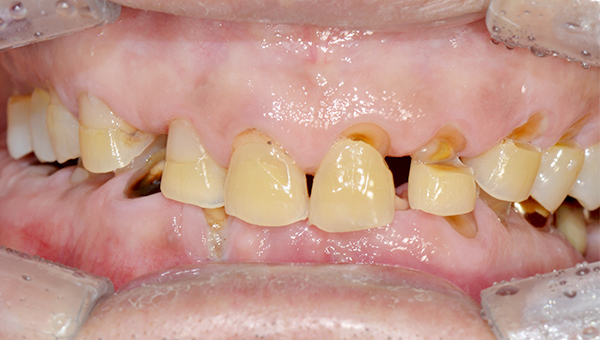

심*복 임플란트 시술 사례

전체 임플란트

2024.12.05

치료 전

2025.05.30

치료 후